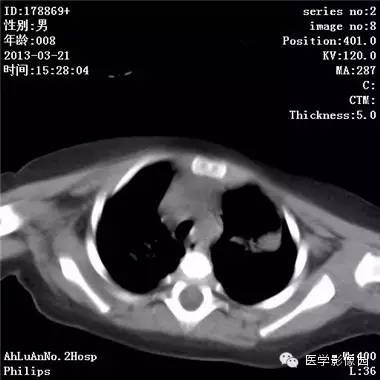

影像学表现